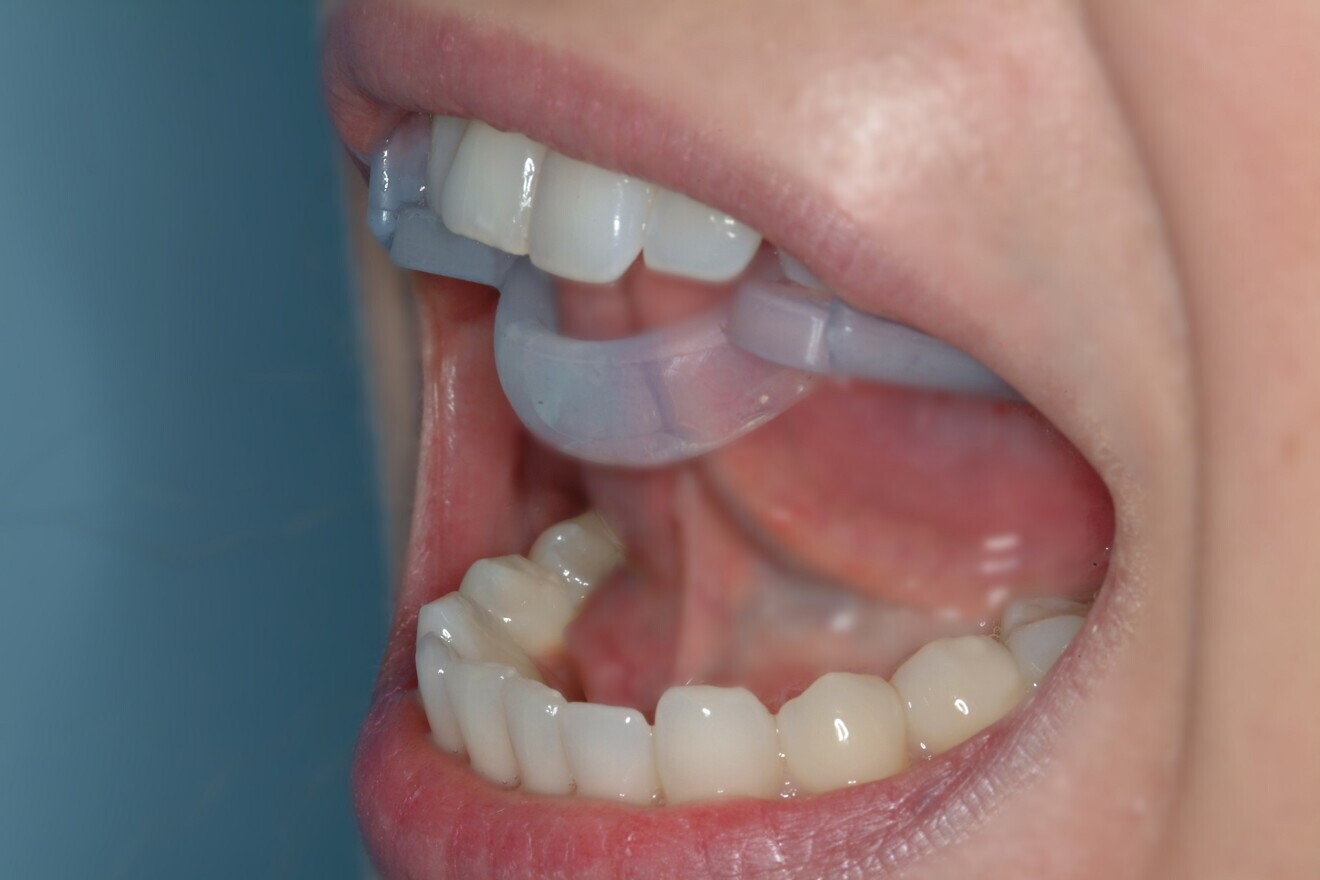

We begin with swallowing rehabilitation with Froggymouth. Froggymouth must be worn for 20 minutes per day for a minimum of 21 days continuously (Fig. 8). We must also help the patient to get rid of bad oral habits. Simultaneously, we must decondition the masticatory muscles and relieve the TMJs with an occlusal device. The Ri.P.A.Ra. lingual ring can be used as a night guard before and during treatment, as well as for physiotherapeutic exercises and osteopathic treatment (Fig. 9).37

1. tongue dysfunction therapy with Froggymouth (Fig. 16);